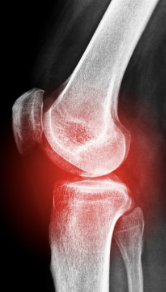

무릎 관절염 증상 원인 치료방법

무릎 관절염 증상 원인 치료방법 등 무릎 관절염과 관련된 정보를 알아보도록 하겠습니다. 무릎 관절은 우리 몸에서 가장 중요하고 복잡한 관절 중 하나입니다. 무릎 관절은 다리의 움직임을 가능하게 하고, 체중을 지탱하고, 충격을 흡수하는 역할을 합니다. 그러나 무릎 관절은 나이가 들면서 마모되거나, 부상이나 질병으로 인해 손상될 수 있습니다. 이러한 경우에는 무릎 관절의 기능이 저하되고, 통증이나 염증이 발생할 수 있습니다.